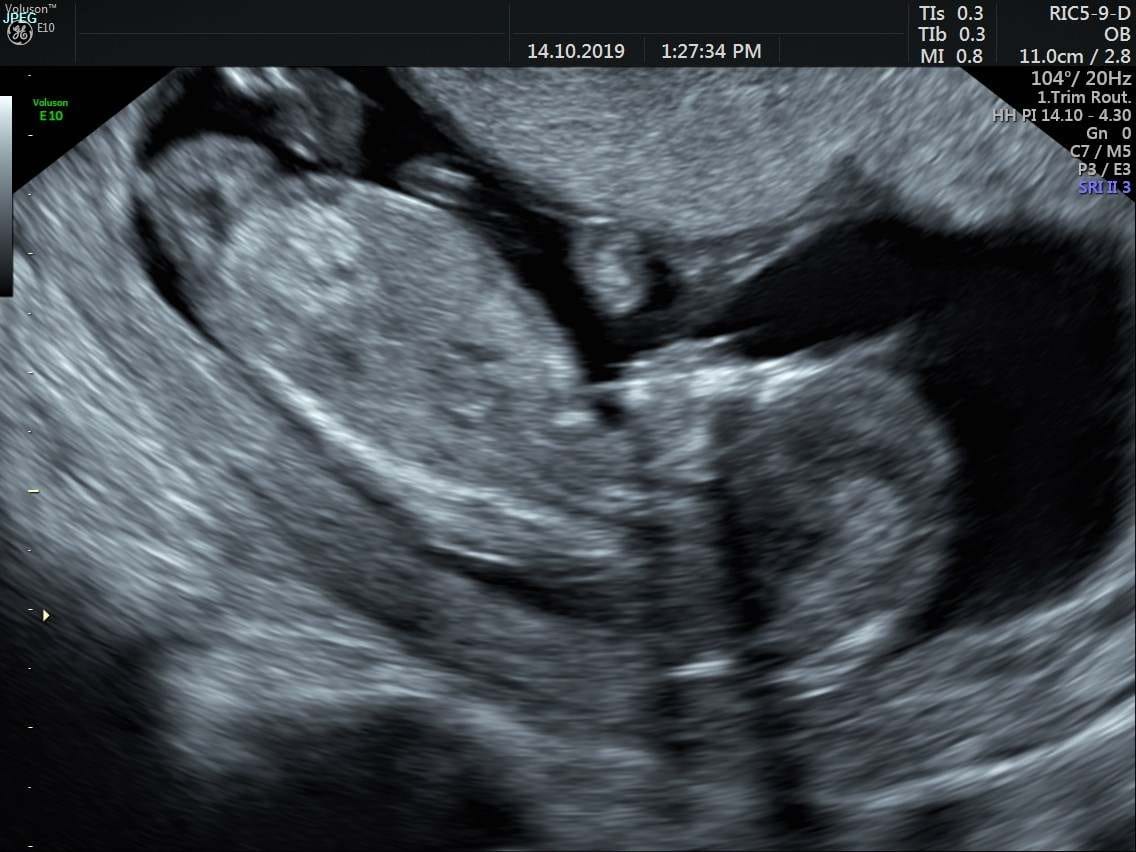

Ahojky holky 🙂 tak prvni screen je za nami a dopadl dobre 🙂 jsme o den mladsi nez podle ms ale jsme zdravi a rosteme jako z vody 🙂 dalsi obavy za nami,kdo uz to ma take za sebou a je rad? :D 🙂 vsem co to teprve ceka preji hodne moc stesti,videt to male a slyset srdicko byl nejkrasnejsi pocit v zivote,manzel tam byl se mnou a mel slzy v ocich,jsme po jednom SP proto to bereme jako dar 🙂

@kackaa91 Urcite bude neboj 🙂 Tak s hematomem to je dobra zprava 🙂) je to doba a rozumim ti ja byla naposledy u sveho gynekologa 18.9. a pak az na tom screeningu vcera takze jsem taky cekala skoro mesic a nic jsem nevedela,bylo to nekonecny 🙄 Ano sla jsem na krev zhruba 3 tydny predem a ten ultrazvuk,prisla jsem tam me ho delali vaginalne protoze pres brisko to nebylo videt tak jak melo,bohuzel nejsem hubena ale plnostihla a tak rikal ze tak to bude jistejsi 🙂 na recepci jsem nahlasila vysku a vahu. Ultrazvuk trval asi zhruba 10-15 minut poradne ti vsechno ukaze,sijove projasneni a nosni kustku to je nejdulezitejsi,meri ten plod jestli ma spravne rozmery a pak ti ukazuje ruzne casti tela nohy a ruce,pater,srdicko rika ti kde to je umisteno a jestli to je spravne,pak mi pustil i zvuk abych slysela srdicko a meril jestli spravne tluce v tech frekvencich co ma 🙂 bohuzel pohlavi si jeste netroufl rict nekde ti ho povi a nekde to jeste neni poradne videt 🙂 no a pak to dal do PC vysledky z ultrazvuku a z krve a napise ti zpravu s temi vysledky,me to treba jeste podrobne vysvetlil jake mam hodnoty a ze test je negativni a to je spravne. Takze vyloucil Downuv syndrom a Edwardsnuv syndrom. No a ted si musim hlidat ten 2 screening to je zase ve 2 trimetsru a tam se odhlai vice a i vyvojove vady srdicka a tak dale. No nekdo uz na nej pry nechodi ale ja urcite pujdu chci mit jistotu 🙂 a to probiha stejne zase krev a ultrazvuk ❤